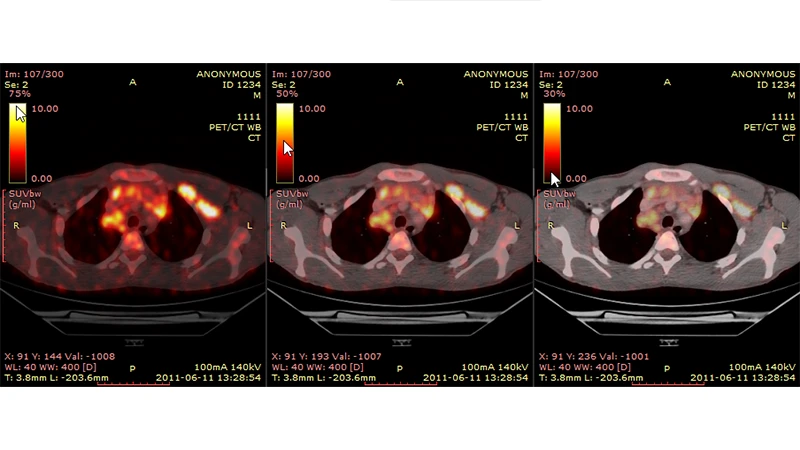

Modern scanners often combine PET and CT into a single hybrid machine (PET/CT). The patient undergoes both a PET scan and a CT scan in one session. The resulting images are then fused together by a computer. This provides the best of both worlds: the PET scan shows areas of high metabolic activity (the function), and the CT scan provides the detailed anatomical map (the form), allowing a radiologist to see exactly where the physiological activity is occurring.

A fused PET/CT image of a cancer patient, showing bright spots of metabolic activity overlaid on a detailed anatomical CT image